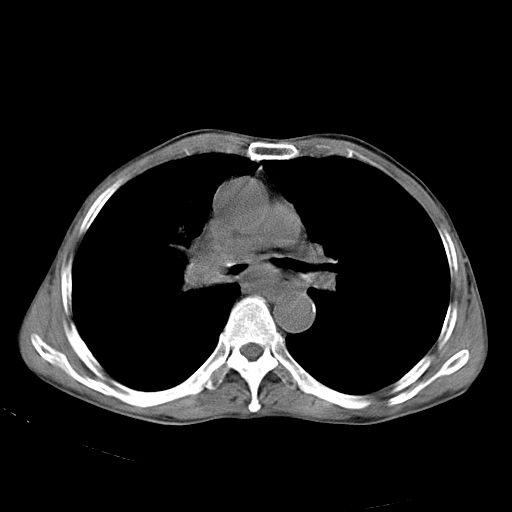

以下是引用苯小孩在2007-5-24 12:47:00的发言:[br]右侧肺门处不均匀密度软组织块影,远端肺组织见斑片模糊影,纵隔内淋巴结明显肿大,边界不清.<纵隔窗第12层面支气管内似见软组织结节>[br]考虑:1、右侧中央性肺癌并阻塞性肺炎并纵隔淋巴结转移可能性大.建议强化或纤支镜进一步检查.[br]2、隆突下淋巴结肿大/食道病变?请做鉴别检查.

以下是引用zhangzhongshou在2007-5-24 12:55:00的发言:[br]1、右肺中叶中心型肺癌并右肺门、隆突下、纵隔淋巴结转移。右肺中叶阻塞性肺炎。

以下是引用jw-830在2007-5-24 15:24:00的发言:[br][br] [br] 考虑右肺中央型肺癌并阻塞性炎症,右肺门及纵隔淋巴结转移。 [br] [br][br]